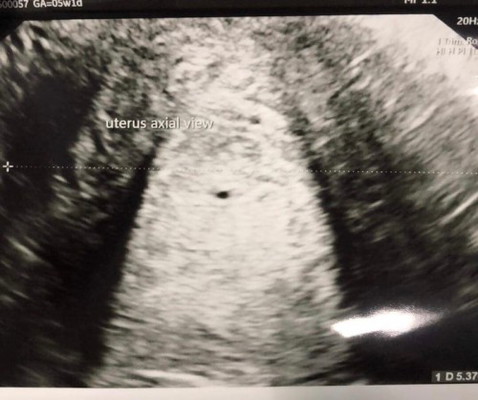

ท้อง 5 w ไปอัลตราซาวด์ช่องท้องหมอบอกว่าถุงตั้งครรภ์เล็กมาก ตรวจช่องคลอดหมอบอกว่าไม่แน่ว่ามีการตั้งครรภ์มั้ย แม่ๆคนไหนเป็นบ้าง

ท้องแรกกังวลมา

อายุครรภ์ยังเล็ก รออีก 2-3 สัปดาห์ดูก่อนค่าแม่